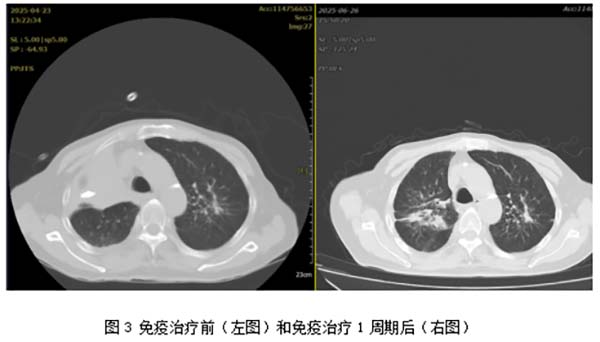

虽然患者再次转危为安,但肿瘤生长速度之快,超出了所有人的预期。经过再次沟通,抱着一线希望,患者和家属同意尝试进行全身治疗。在进行分子病理检测后,发现肿瘤组织PD-L1表达TPS 95%,这提示患者对免疫治疗可能高度敏感。结合患者的一般情况和病理结果,医生制定了免疫单药治疗的方案。2025年6月9日,患者进行第一次的免疫治疗(信迪利单抗200mg)后顺利出院。

2025年6月29日,计划中的第二周期治疗时间到了,刘大爷如约再次住院。复查胸CT的结果超出了所有人的预期,不仅肿瘤没有再疯长,而且明显缩小,原本被肿瘤阻塞的右上叶复张了(图3)!此时的刘大爷和家人,信心满满,接受了第二次的免疫治疗,顺利出院。目前,刘大爷正在随访当中,将按计划进行后续治疗。